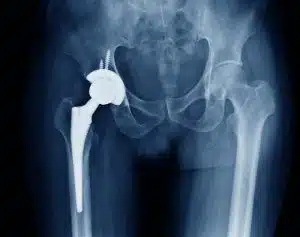

ما هي عملية تغيير مفصل الفخذ؟

عملية تغيير مفصل الفخذ هي إجراء جراحي يستبدل فيه المفصل التالف بمفصل صناعي لاستعادة الحركة وتخفيف الألم، وذلك نتيجة لأسباب مثل:

- التهاب المفاصل الروماتويدي.

- الفصال العظمي (تآكل الغضروف).

- تنخر العظام (نقص التروية الدموية).

- الكسور أو مشاكل وراثية.

تتم جراحة تغيير مفصل الفخذ تحت إشراف دكتور عمرو أمل أحسن دكتور عظام في القاهرة، وينصح بالفحوصات اللازمة قبل العملية والقيام بتمارين العلاج الطبيعي بعدها.

المفاصل الصناعية هي بديل للمفاصل الطبيعية التالفة، وتُصنع من مواد عالية الجودة كالبلاستيك والمعدن.

يعد دكتور عمرو أمل (استشاري جراحة العظام والمفاصل واصابات الملاعب) من أفضل الأطباء في تركيب المفاصل الصناعية في مصر، مثل عمليات تغيير مفصل الحوض وتغيير مفصل الكوع، لخبرته الواسعة واستخدامه لأحدث المعدات.